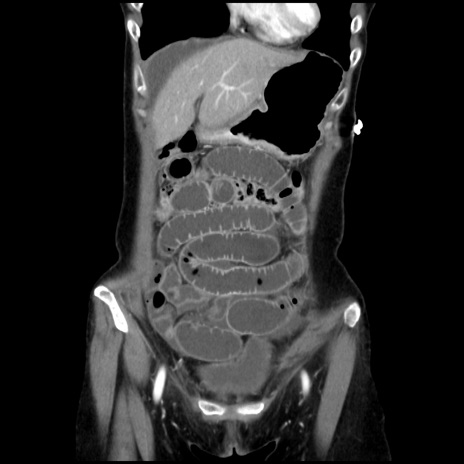

横断像

【症例】40歳代 女性

【主訴】上腹部痛、嘔気・嘔吐

【現病歴】約9時間前頃から急に上腹部痛、嘔気、嘔吐が出現。改善しないため救急要請。

【既往歴】子宮頚癌(広汎子宮全摘術、放射線療法)、腸閉塞

【身体所見】腹部:平坦、軟、腸雑音亢進、上腹部を中心に腹部全体に圧痛あり。

【データ】WBC 8400、CRP 0.03